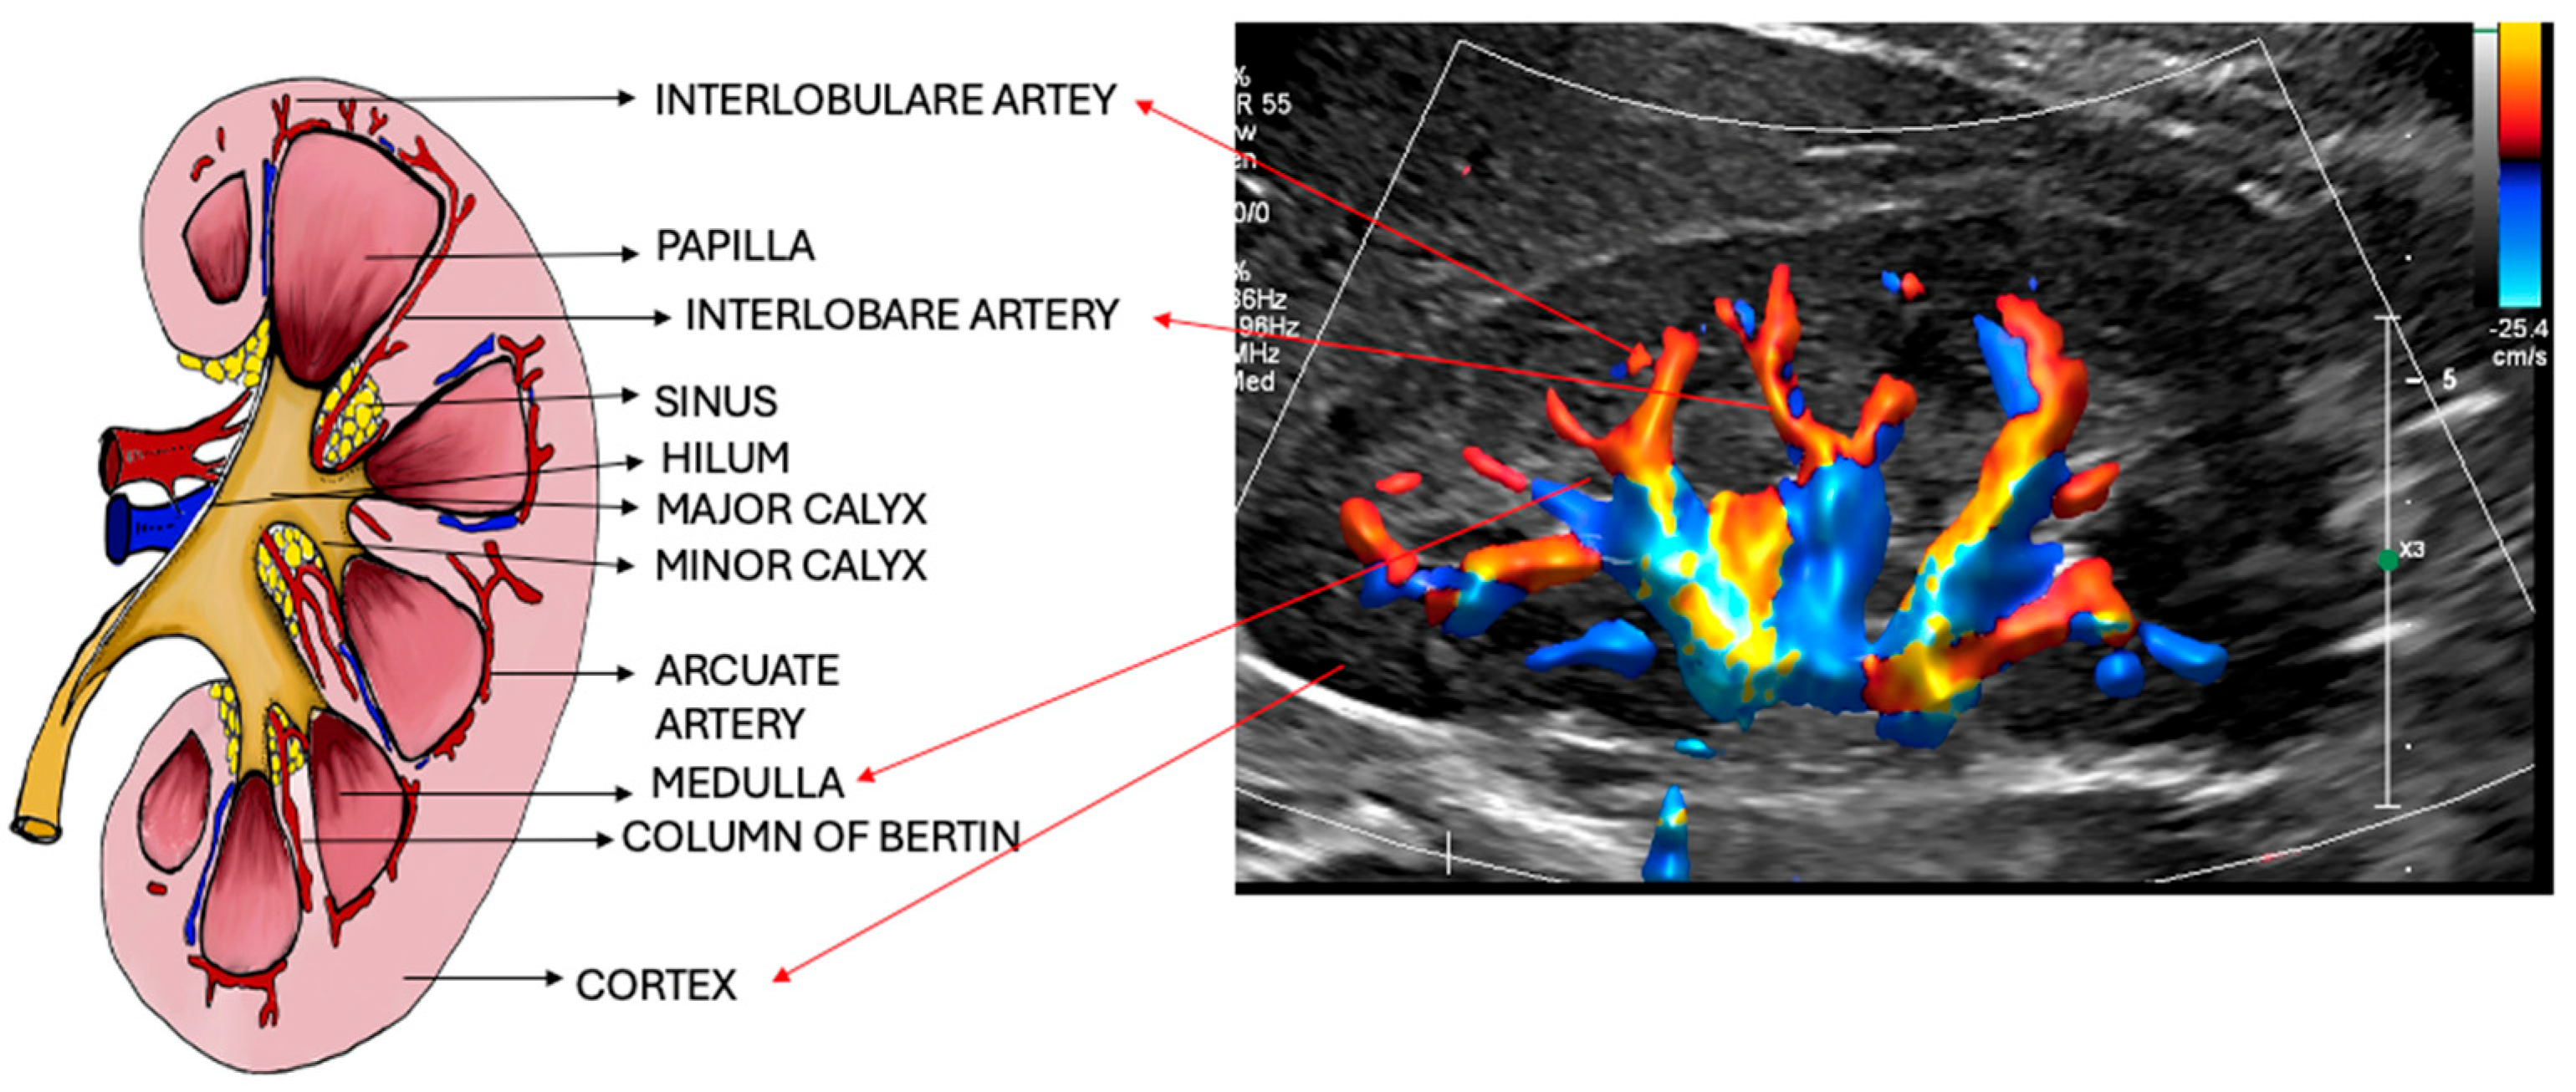

4. Intrarenal Anatomy

4.1. Renal Vascular Anatomy

9. Doppler Ultrasound (Vasculature Assessment)